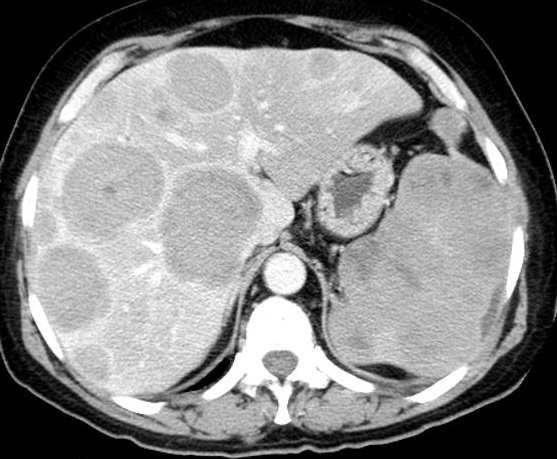

Image radiologique TDM phase

veineuse d'une lymphone primaire( large B cell )

maligne de la rate avec aspect des masses nodulaires

hypodensites heterogene de la rate et du foie . La

rate est volumineuse a bord encapsule lobulaire , la

lesion sera en vue facile au phase veineuse (

portal veinous phase ) |